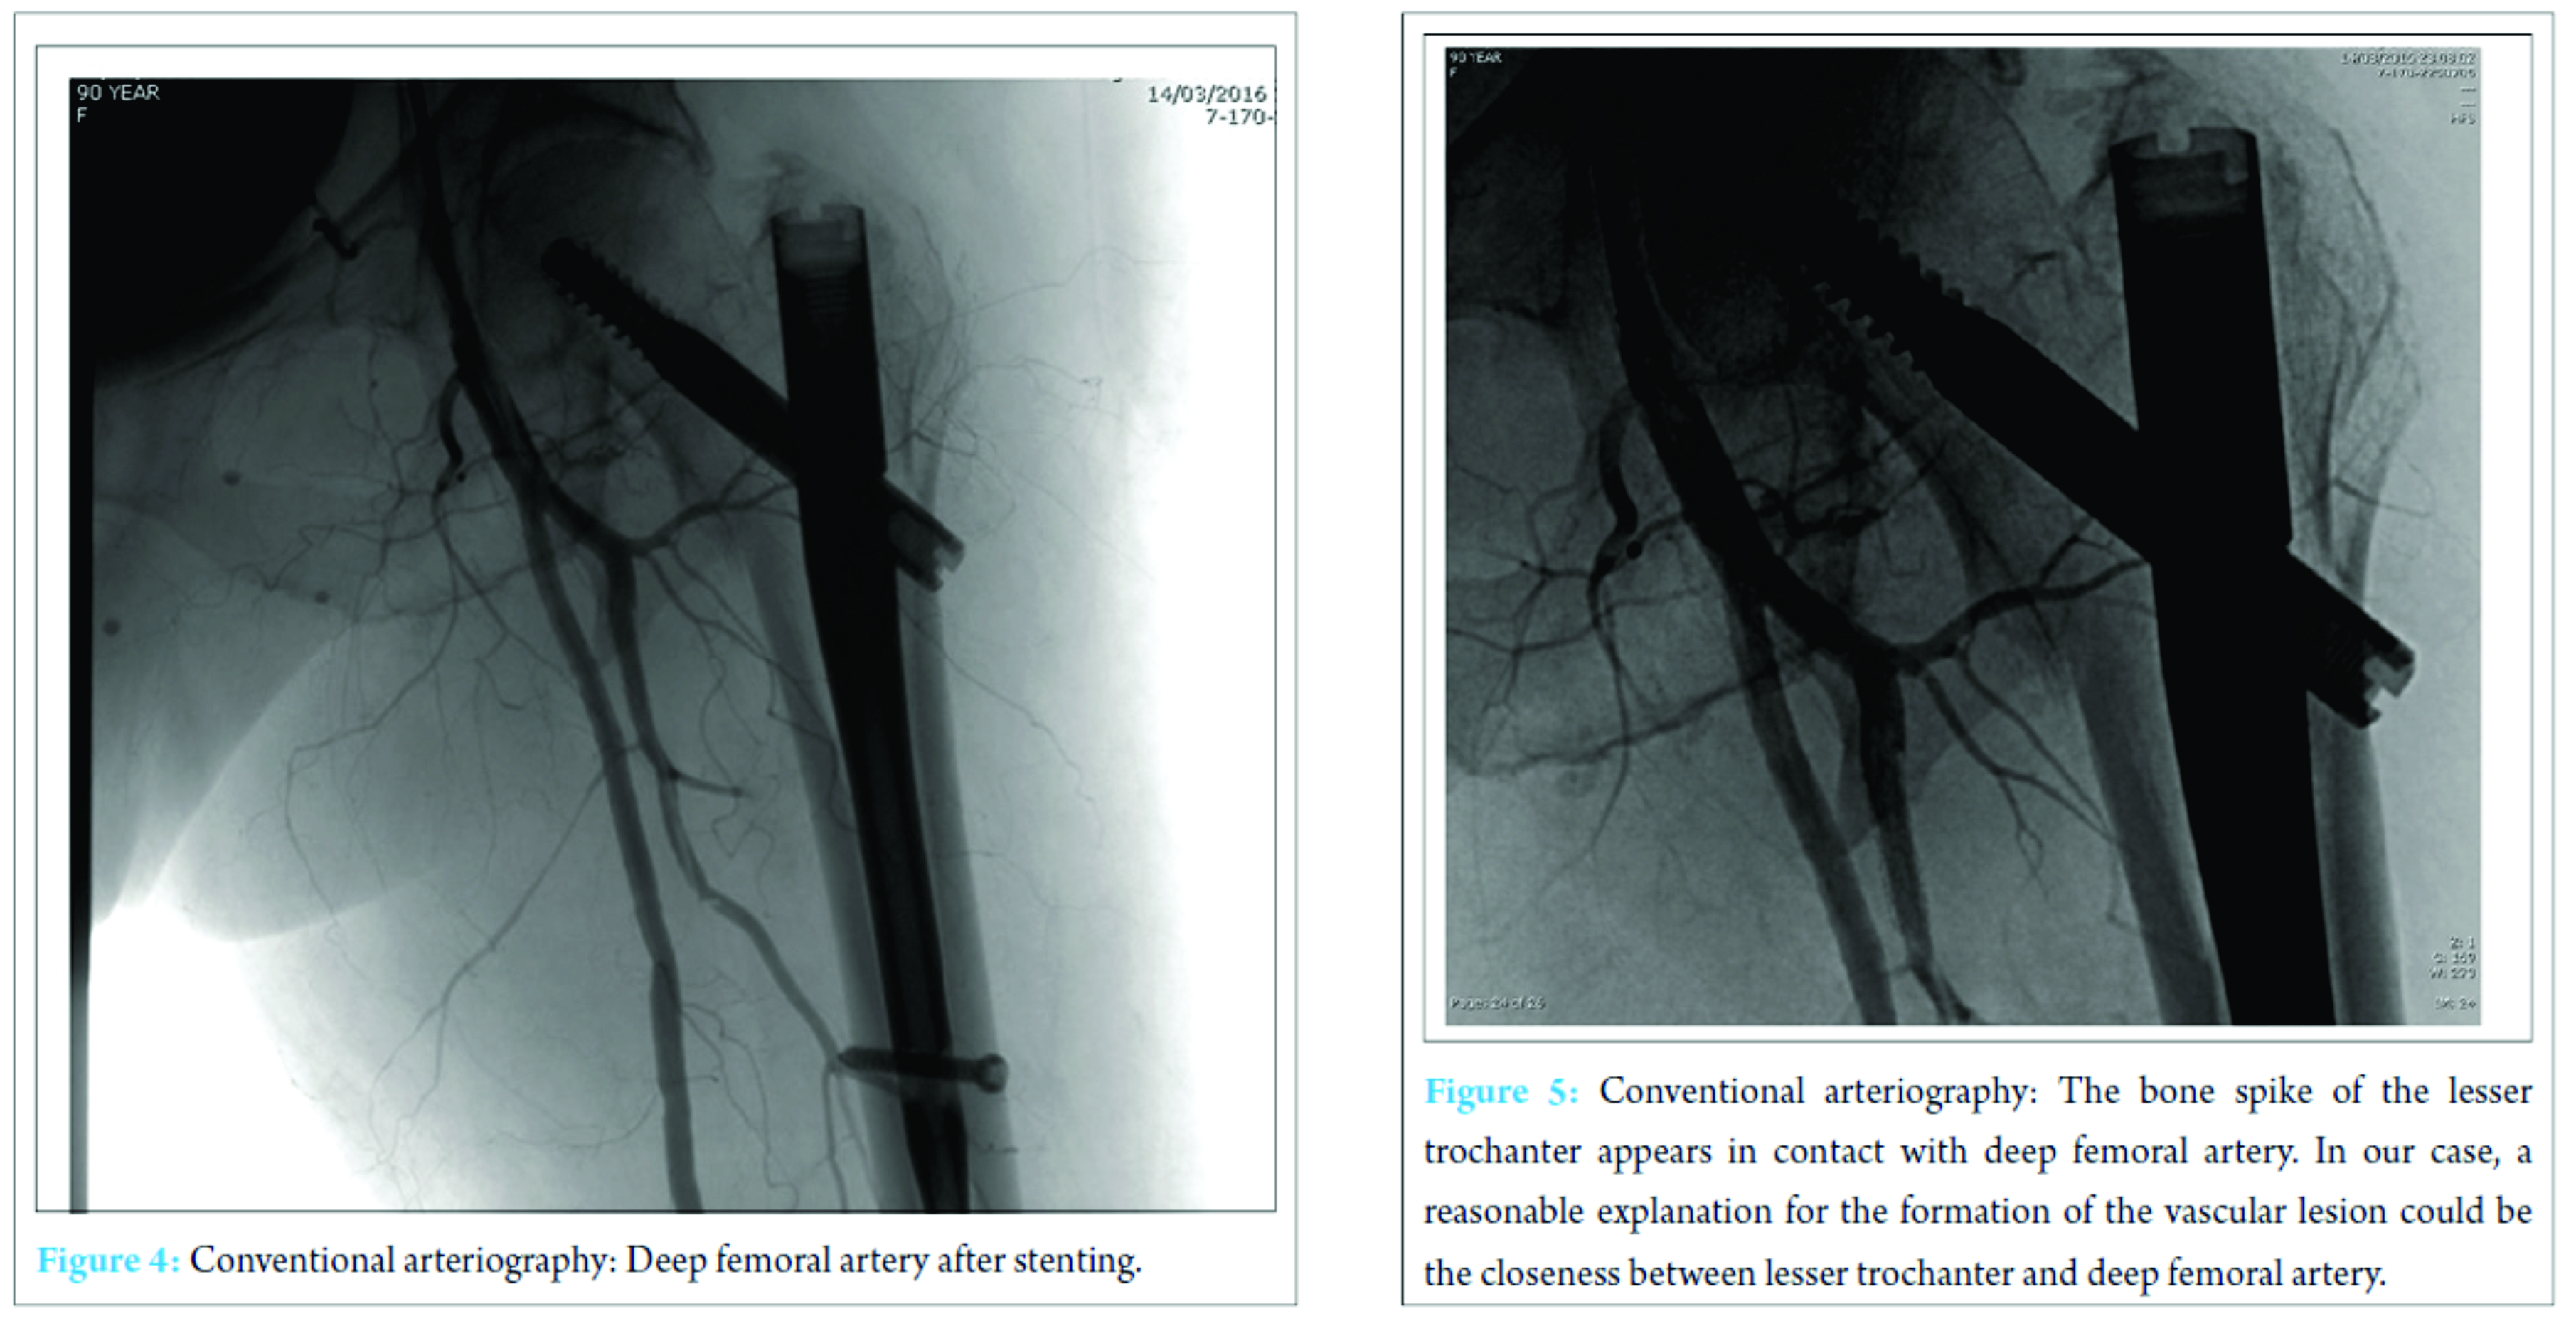

Therefore, a stent was placed (Fig. 4). After this procedure, the clinical conditions improved and the patient was discharged 4 days later with stable blood exams. On the last clinical control, 3 months after the stenting, the patient was feeling well and had started physical rehabilitation.

Hip fractures in older patients are the most common fractures treated by orthopedic surgeons. The incidence increases with age and degree of osteoporosis. The most frequent traumatic mechanism is a low energy fall from a standing height [5]. Proximal femoral fractures may be treated using different techniques of fixation. Screws or partial arthroplasty proves to be efficient for the synthesis of intracapsular fractures, whereas nails and plates are the most commonly employed for extracapsular fractures. In our case, we treated a 31-A2 fracture with a gamma nail. The role of intramedullary fixation for the treatment of this kind of fracture is still debated. Anyway, gamma nail is often preferred to slide hip screws, especially, because of easy handling instrumentarium and implant versatility. According to many authors, gamma nail has proved to be a safe and efficient fixation of pertrochanteric fractures [6]. Vascular complications after intramedullary fixation of pertrochanteric fracture are rare. These complications can develop after fracture during intramedullary hip nailing and displacing of bone fragment during fracture or repair. Furthermore, some authors suggest that manipulation of atherosclerotic vessels of the leg on the fracture table may injure their brittle endothelium with an increased risk of bleeding and thromboembolic events. Vascular injuries may be hemorrhagic or thrombotic, acute (hemorrhage), or delayed (pseudoaneurysm formation). Regardless of the type of vascular lesion, the most frequently injured vessel is the deep femoral artery followed by its perforating branches [4]. False aneurysms or pseudoaneurysms are surrounded by a thin fibrous capsule in contrast to true aneurysms that consist of the true layers of the arterial wall. The fibrin capsule is made of soft tissues and/or hematoma adjacent the vessel. There is a high risk of enlargement and rapture of the vessel, in particular, when the dimension of the pseudoaneurysm is superior to 3 cm. Rapid expansion, infection, skin or soft tissue necrosis, neuropathy, distal ischemia, pain, or rupture are the most important indications for repair [7]. The incidence of pseudoaneurysm after hip fracture is very low (0.21% of incidence) and rarely reported as a consequence of dislocated bone fragments. According to literature, arterial damages can occur because of bone spikes, tip of the screws, drills, displaced implants, and retraction of surrounding tissue [8]. In our report, X-ray imaging after surgery shows the proximal migration of lesser trochanteric fragment, due to the action of iliopsoas that fits on the lesser trochanter, near the pseudoaneurysm. According to symptoms and instrumental studies, it seems that dislocated fragment may have damaged the deep femoral artery that lies near proximal femur (Fig. 5). However, in almost 25% of pertrochanteric fracture, the lesser trochanter was involved, but vascular complications rarely occur, probably thanks to vessels elasticity. Clinical manifestations of a false aneurysm after hip fracture have been reported between 3 days and 14 years, but in cases of dislocated lesser trochanter being responsible for vascular lesion, these manifestations are more frequent between 18 and 36 days. Probably clinical appearance of the pseudoaneurysm is delayed until the patient starts mobilization that can dislocate bone fragments. In this case, we found the pseudoaneurysm 16 days after surgery, below the average reported in literature. Often it is difficult to identify this complication because of non-specific symptoms including pain, edema, and swelling that are common after hip surgery. We should suspect a pseudoaneurysm if the patient presents falling of hemoglobin level, pulsatile swelling, or venous engorgement, and we can diagnose this complication by duplex ultrasound (US), conventional angiography, and computed tomography (CT) angiography [9]. US is the method of choice for diagnosis of pseudoaneurysm with sensitivity between 94 and 97%. As in our case, conventional angiography (or CT-angiography) can be useful to confirm and to better define the vascular lesion. There are numerous treatment options for deep femoral artery pseudoaneurysm: Conservative management for smaller aneurysms, US-guided compression, percutaneous US-guided thrombin injection, percutaneous US-guided collagen injection, insertion of coils, covered stents, and open surgery [10]. The treatment we chose consisted in positioning an endovascular stent covered by polytetrafluoroethylene. After the procedure, symptoms improved and the patient was able to resume the rehabilitation program a few days later.